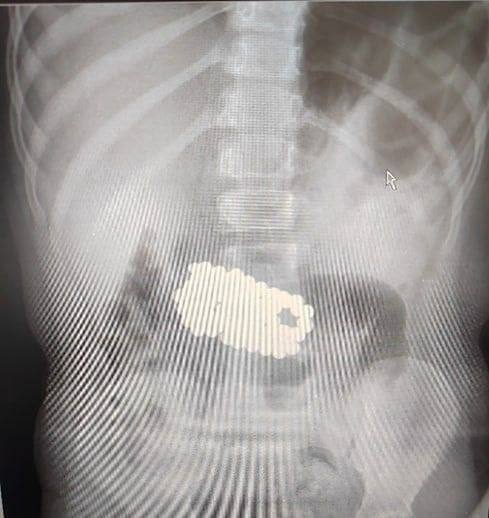

Подмосковные врачи извлекли 100 магнитных шариков из желудка 5-летней девочки

Во время игры ребенок взял игрушку старшего брата - неокуб, состоящий из магнитов. Девочка проглотила 100 магнитных шариков, а родителям рассказать боялась.

Операция длилась около трех часов. Все инородные предметы благополучно достали.